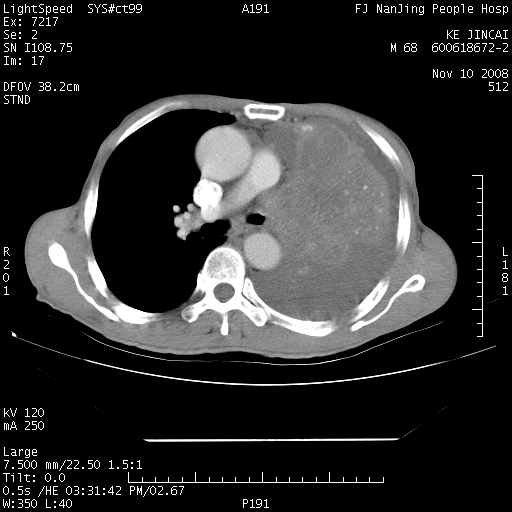

是个很有看头的病例,咋人气那么不旺?没多少人兴趣呢?这个病例几大怪:1   恶性肿瘤侵犯心肌左房怪,心肌一般不会被恶性肿瘤侵犯吧?2   左下肺均匀实变怪,内无含气,有别一般不张实变,含气肺泡完全为液体取代,而非一般不张实变的肺萎陷,冷不丁还以为是肿大的脾脏3   肿瘤本身怪,像tb肺不张4   这么有看头的病例没人气怪。呵呵。

左肺恶性肿瘤侵犯肺动脉,左心房内瘤栓,胸膜转移。

左肺恶性肿瘤侵犯肺动脉,左心房内瘤栓,胸膜转移,少见,学习了。